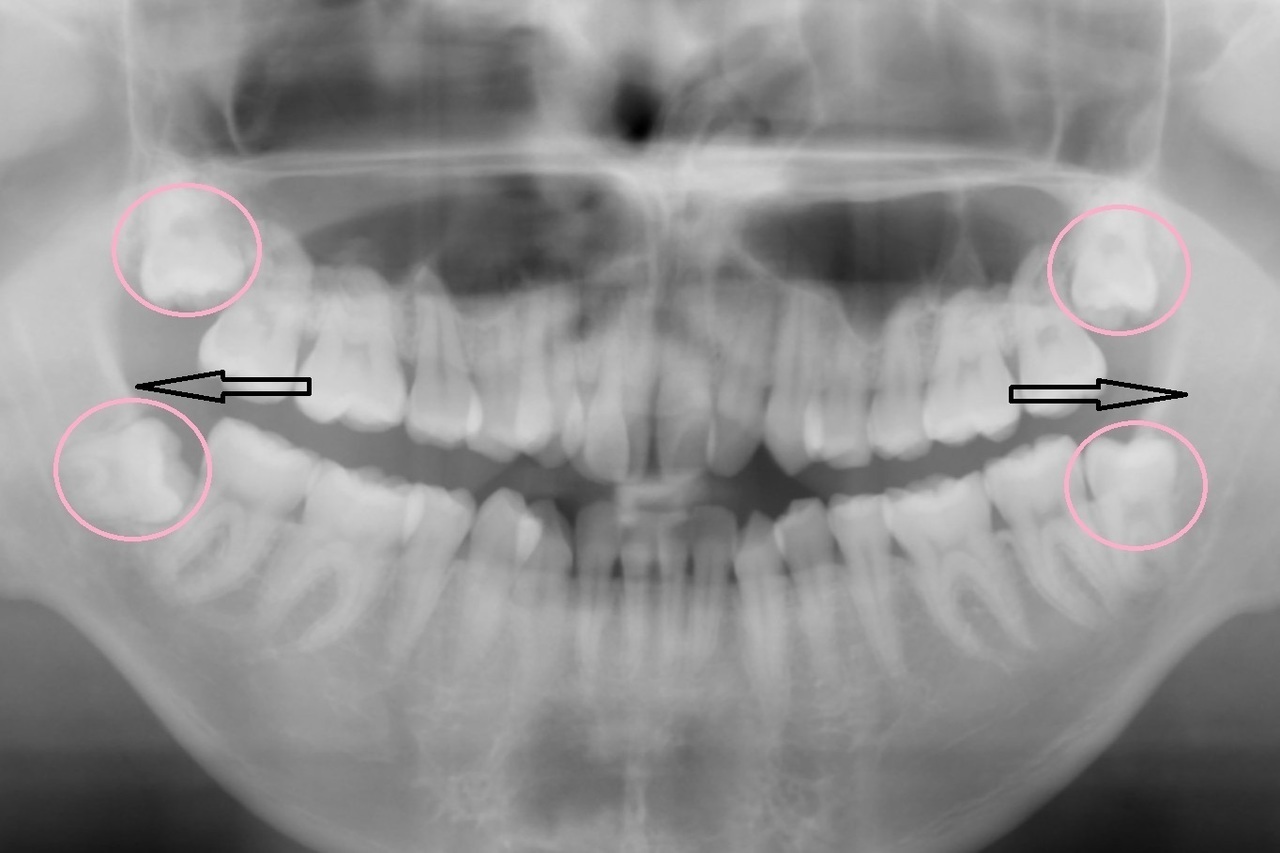

下のレントゲンにイメージを図示しています

もう一つ大きな注意点があります

初診時に大きく中に入っていた上の右2番目(向かって左側2番目)の前歯

これを理想と思われる位置にもっていきたかったのですが

初診時のCT(3Dのレントゲン)を細かく分析すると

理想の位置に移動させてしまうと

最悪歯が骨から抜けてしまい抜歯に至る可能性がありました

(専門用語でフェネストレーションといいます)

矯正治療をしたことで抜歯に至るというのは本末転倒です

今回は理想の位置よりもわずかに中に入った位置で矯正終了となることを

事前に患者さまにご了承いただいてからスタートしております

現在ではCTとクリンチェックを結合することができるので

もっとわかりやすく確認できるようになっていますが

下にCTの画像を載せておきます

〇部分が骨がないところ 矢印の歯を理想の位置までは動かせません